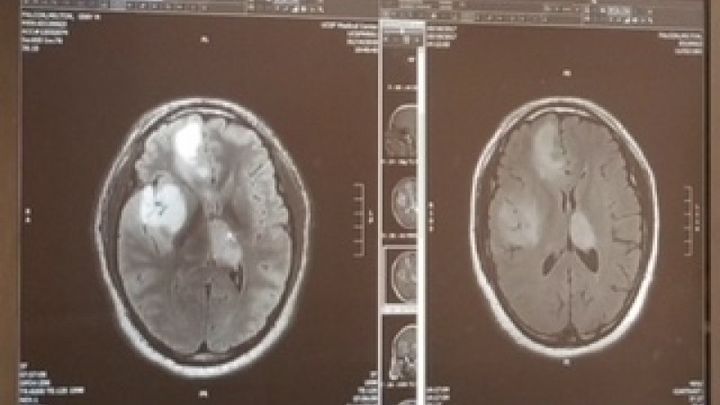

I worked in restaurants and as a delivery driver. One day, I started to feel ill, went to the doctor... got diagnosed

with Anaplasic Astrocytoma in several areas of my brain, specifically I have 4 malign tumors (cerebral cancer).

un dia empece a sentir malestares, fui al medico y fui diagnosticado con astriocitoma anaplasico, en diferentes areas de mi cerebro, especificamente tengo 4 tumores malignos (cancer en el cerebro).